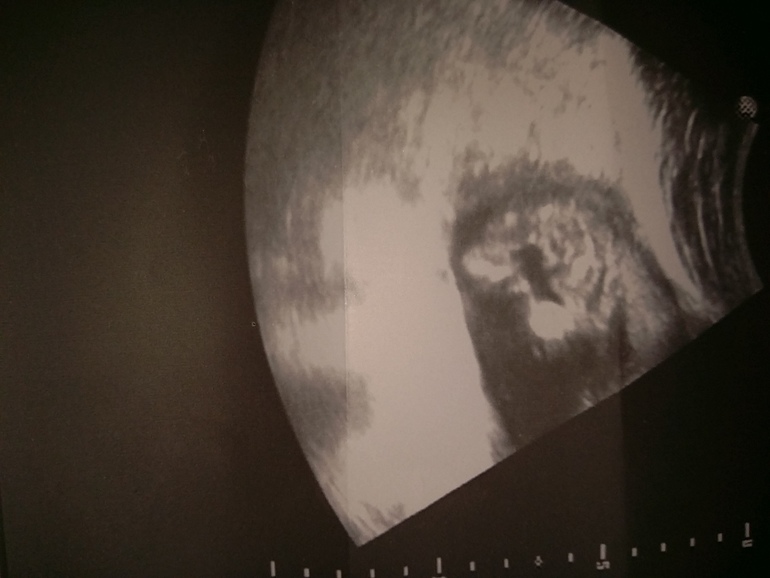

18 недель узи

Результаты: УЗИ, КТГ, доплера, скринингаДобрый вечер, девочки. Вот пришла сегодня с узи.) Сказали- девочка. С

Ракурс сложный. Я подумала, что мальчик. Потом прочитала вас, что девочка. Значит девочка)) врачу виднее было! Мне определили в 16 недель.